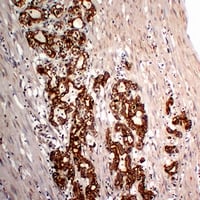

(Immunohistochemical analysis of Cytokeratin 18 staining in human colon carcinoma formalin fixed paraffin embedded tissue section. The section was pre-treated using heat mediated antigen retrieval with sodium citrate buffer (pH 6.0). The section was then incubated with the antibody at room temperature and detected using an HRP conjugated compact polymer system. DAB was used as the chromogen. The section was then counterstained with haematoxylin and mounted with DPX.)